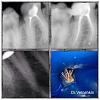

Денис481 Опубликовано 12 июня, 2013 Поделиться Опубликовано 12 июня, 2013 Вот пришла пациентка сделал снимок рф на половину в каналах,одел кофер-самолет)))облил жидким кофером,убрал старую пломбу,с устьев чуть убрал уз,потом залил жидкостью для распломбировки,начал с патфайлов,чуть зашел в устья затем мту,и латералка Ссылка на комментарий

ger_berra Опубликовано 12 июня, 2013 Поделиться Опубликовано 12 июня, 2013 (изменено) И в МЩ ушёл не туда Изменено 12 июня, 2013 пользователем ger_berra Ссылка на комментарий

Денис481 Опубликовано 13 июня, 2013 Автор Поделиться Опубликовано 13 июня, 2013 Я тоже думал не туда,я для этого его отдельно сделал с инструментом на 3 фото,отжигаю потом,если закрывает обзор то сразу Ссылка на комментарий

Денис481 Опубликовано 13 июня, 2013 Автор Поделиться Опубликовано 13 июня, 2013 Вот мне показалось что так,и я его можно сказать пассивно разрабатывал,под собственным весом эндомотор шел Ссылка на комментарий

ger_berra Опубликовано 13 июня, 2013 Поделиться Опубликовано 13 июня, 2013 Вот мне показалось что так,и я его можно сказать пассивно разрабатывал,под собственным весом эндомотор шелВ перфу да,очень хорошо под собственным весом идёт,пассивненько так .Ну ничего,бывает со всеми.ПРосто в следующий раз нужно быть очень внимательным. Ссылка на комментарий

Денис481 Опубликовано 13 июня, 2013 Автор Поделиться Опубликовано 13 июня, 2013 В перфу да,очень хорошо под собственным весом идёт,пассивненько так .Ну ничего,бывает со всеми.ПРосто в следующий раз нужно быть очень внимательным.Мне все таки кажется не перфо Ссылка на комментарий

ger_berra Опубликовано 13 июня, 2013 Поделиться Опубликовано 13 июня, 2013 Мне все таки кажется не перфоМожет и не перфо,но транспортация есть.И паковка рыхловата.Вызовете паца через 6 месяцев и посмотрите. Ссылка на комментарий